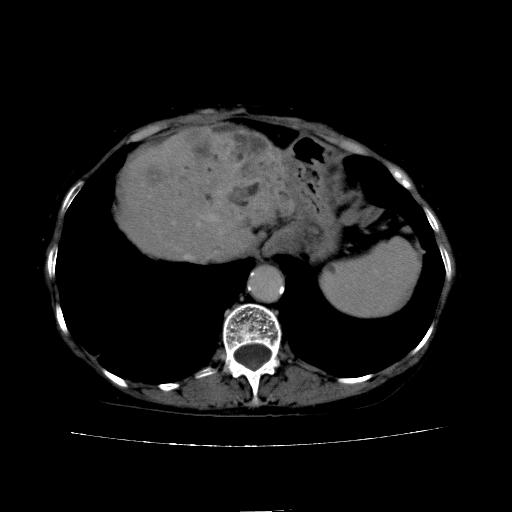

动脉期

看片子胆管里结石,肝上显示的占位会不会是胆管癌?大家帮忙看看,图像不太好,手头的处理文件没有,大致转换了一下,有原始图像数据

1)考虑肝左叶胆管细胞癌并肝内转移。2)肝左叶肝内胆管结石。